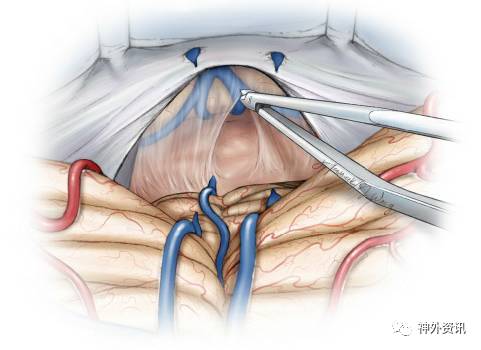

图1. 相对于中线入路,旁正中小脑上入路有许多优势: 1) 颅骨切开术多数不会威胁到优势侧(右侧)横窦和窦汇,更微创;2) 只经过一侧小脑半球进行操作;3) 通常情况小脑蚓部桥静脉受到保护;4) 经小脑外侧的视线斜度更小,为显露肿瘤下极提供较清晰的视线。再次手术可以通过对侧的小脑上入路完成。旁正中或者中线入路可以显露第三脑室后部肿瘤(下图)。

图6. 相对于后正中入路(A),旁正中小脑上入路(B)可以避开几乎所有的小脑蚓部桥静脉。

图7. 后正中入路(A)的显露取决于对山顶的牵拉,而旁正中入路(B)经过的是较低位的外侧小脑。第IV脑神经位于手术区域的下缘。

图12. 中线小脑蚓部桥静脉被电凝、切断。向Galen静脉引流的小脑中央前静脉,位于厚层蛛网膜覆盖的间脑静脉后部,并连接到山顶。手术显露需要牺牲此静脉,其它更多的位于前面的间脑静脉可以保留。注意牵拉、缝合的部位在小脑幕后部,这样的缝合、牵拉可以轻轻将横窦抬起并向上移位。

小脑幕的牵拉、缝合可以抬起横窦,扩大小脑上手术的通道。